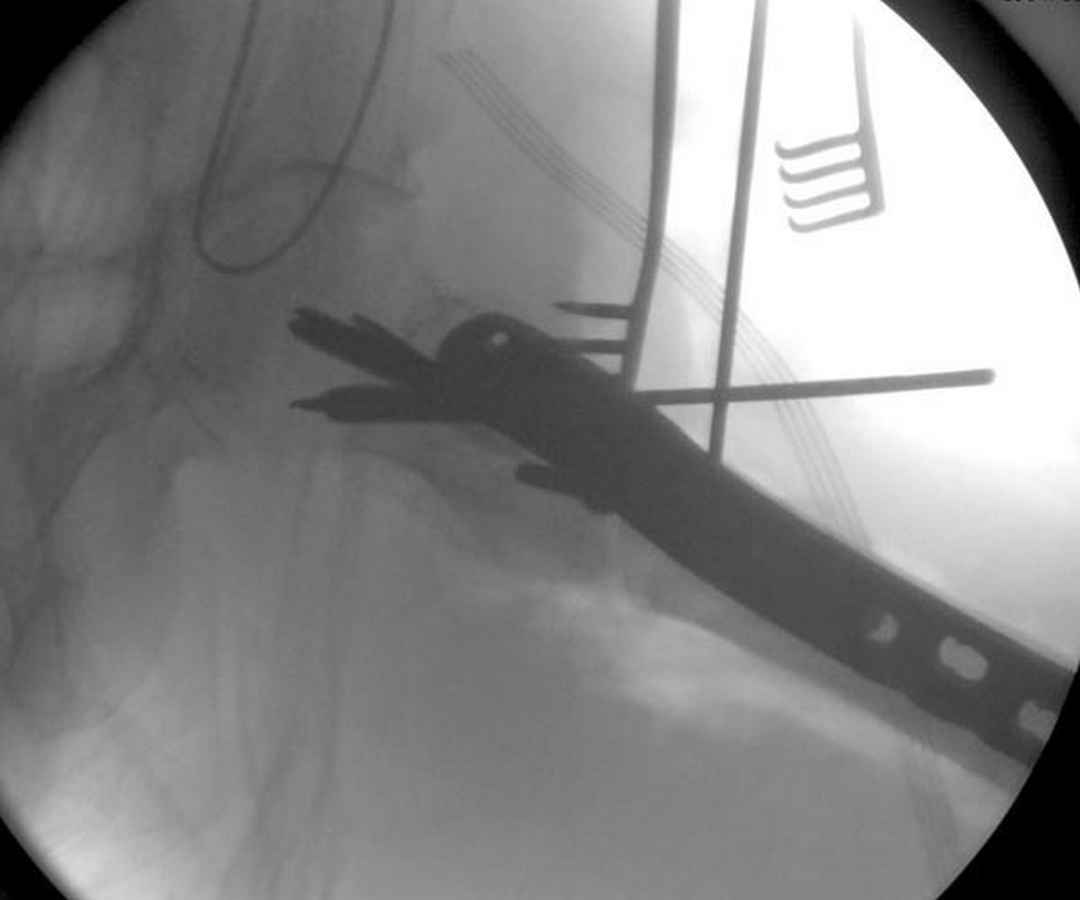

Из фиксаторов, мы бы применили цефаломедуллярные, потому что они "по закону моментов" из-за короткого рычага от центра головки к диафизу и по принципу "головка диафиз" механически лучше выдерживают нагрузки, чем пластины.

Но современные пластины с угловой стабильностью не отстают от медуллярных конструкций. Межфрагментарные шурупы и имплант как нейтрализирующее создаст адекватную фиксацию.

Здесь пара случаев фиксации похожих переломов:

первый высокоэнергетическая травма 36 лет